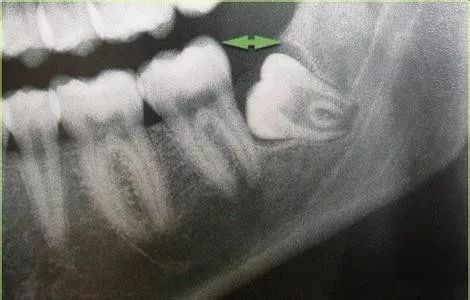

2、拔除智齿会使前面的牙齿向后倒、松动:一般来说,我们的牙齿在一生中都是不停向前移动,而位于牙列最末端的智齿拔除并不会使前面的牙齿松动。